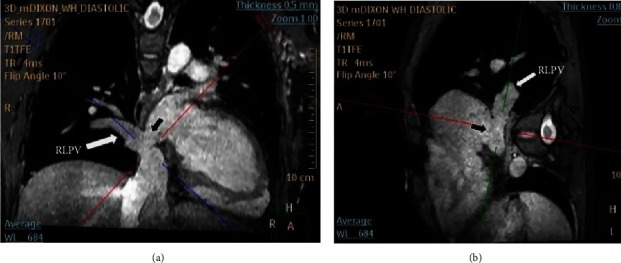

下静脉窦缺损(SVD)较上静脉窦缺损少见。缺损的下缘横跨下腔静脉口,这使得通过双腔静脉插管进行手术修复成为一项技术挑战。无顶右肺静脉的开口是由静脉窦缺陷的房间交通引起的,导致部分肺静脉异常引流(PAPVD)。最近报道了一种新型经导管闭合上位SVD;然而,经导管关闭下位SVD尚未在已发表的文献中报道。在这里,我们报告了首例成功的经导管关闭下静脉曲张,使用裸露和覆盖支架,并将PAPVD重新定向到左心房,以避免肝静脉闭塞。在这一单例报告中,我们仔细地描述了计划过程,手术是如何进行的,以及重新捕获和重新定位迁移支架所采取的步骤。在手术前和手术过程中,仔细选择患者并对肺和肝静脉解剖进行深入评估是取得成功的必要条件。

Inferior sinus venosus defect (SVD) is less common than a superior one. The lower edge of the defect straddles the orifice of the inferior vena cava, and this makes surgical repair via bicaval cannulation a technical challenge. The orifice of the unroofed right pulmonary vein is caused by the interatrial communication in sinus venosus defects which results in partial anomalous pulmonary vein drainage (PAPVD). Novel transcatheter closure of a superior SVD has recently been described; however, transcatheter closure of an inferior SVD has not yet been reported in the published literature. Here, we report the first successful transcatheter closure of an inferior SVD with bare and covered stents and the rerouting of a PAPVD into the left atrium to avoid occlusion of the hepatic veins. In this single-case report, we carefully describe the planning process, how the procedure was performed, and the steps taken to recapture and reposition a migrated stent. Careful patient selection and intensive assessment of pulmonary and hepatic vein anatomy before and during the procedure were necessary to achieve a successful outcome.